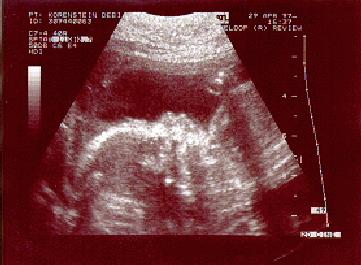

* * * Little Bubsie (P.G.) * * *

This image is of Little Bubsie at 21 Weeks. Little Bubsie is lying on his/her back. His/her head is to the left-hand side of the image, and he/she is waving his/her right hand. You can clearly see Little Bubsie's profile - his/her nose, mouth, etc. and some of his/her torso. His/her right hand is raised towards the right-hand side of the image, and his/her fingers can be seen towards the top of the image.

Little Bubsie is due, P.G., September 8th 1997

One good looking fetus, no?

If any of you out there can identify Little Bubsie's sex from this image (which I seriously doubt that you can from the upper part of the body) - then we aren't interested!